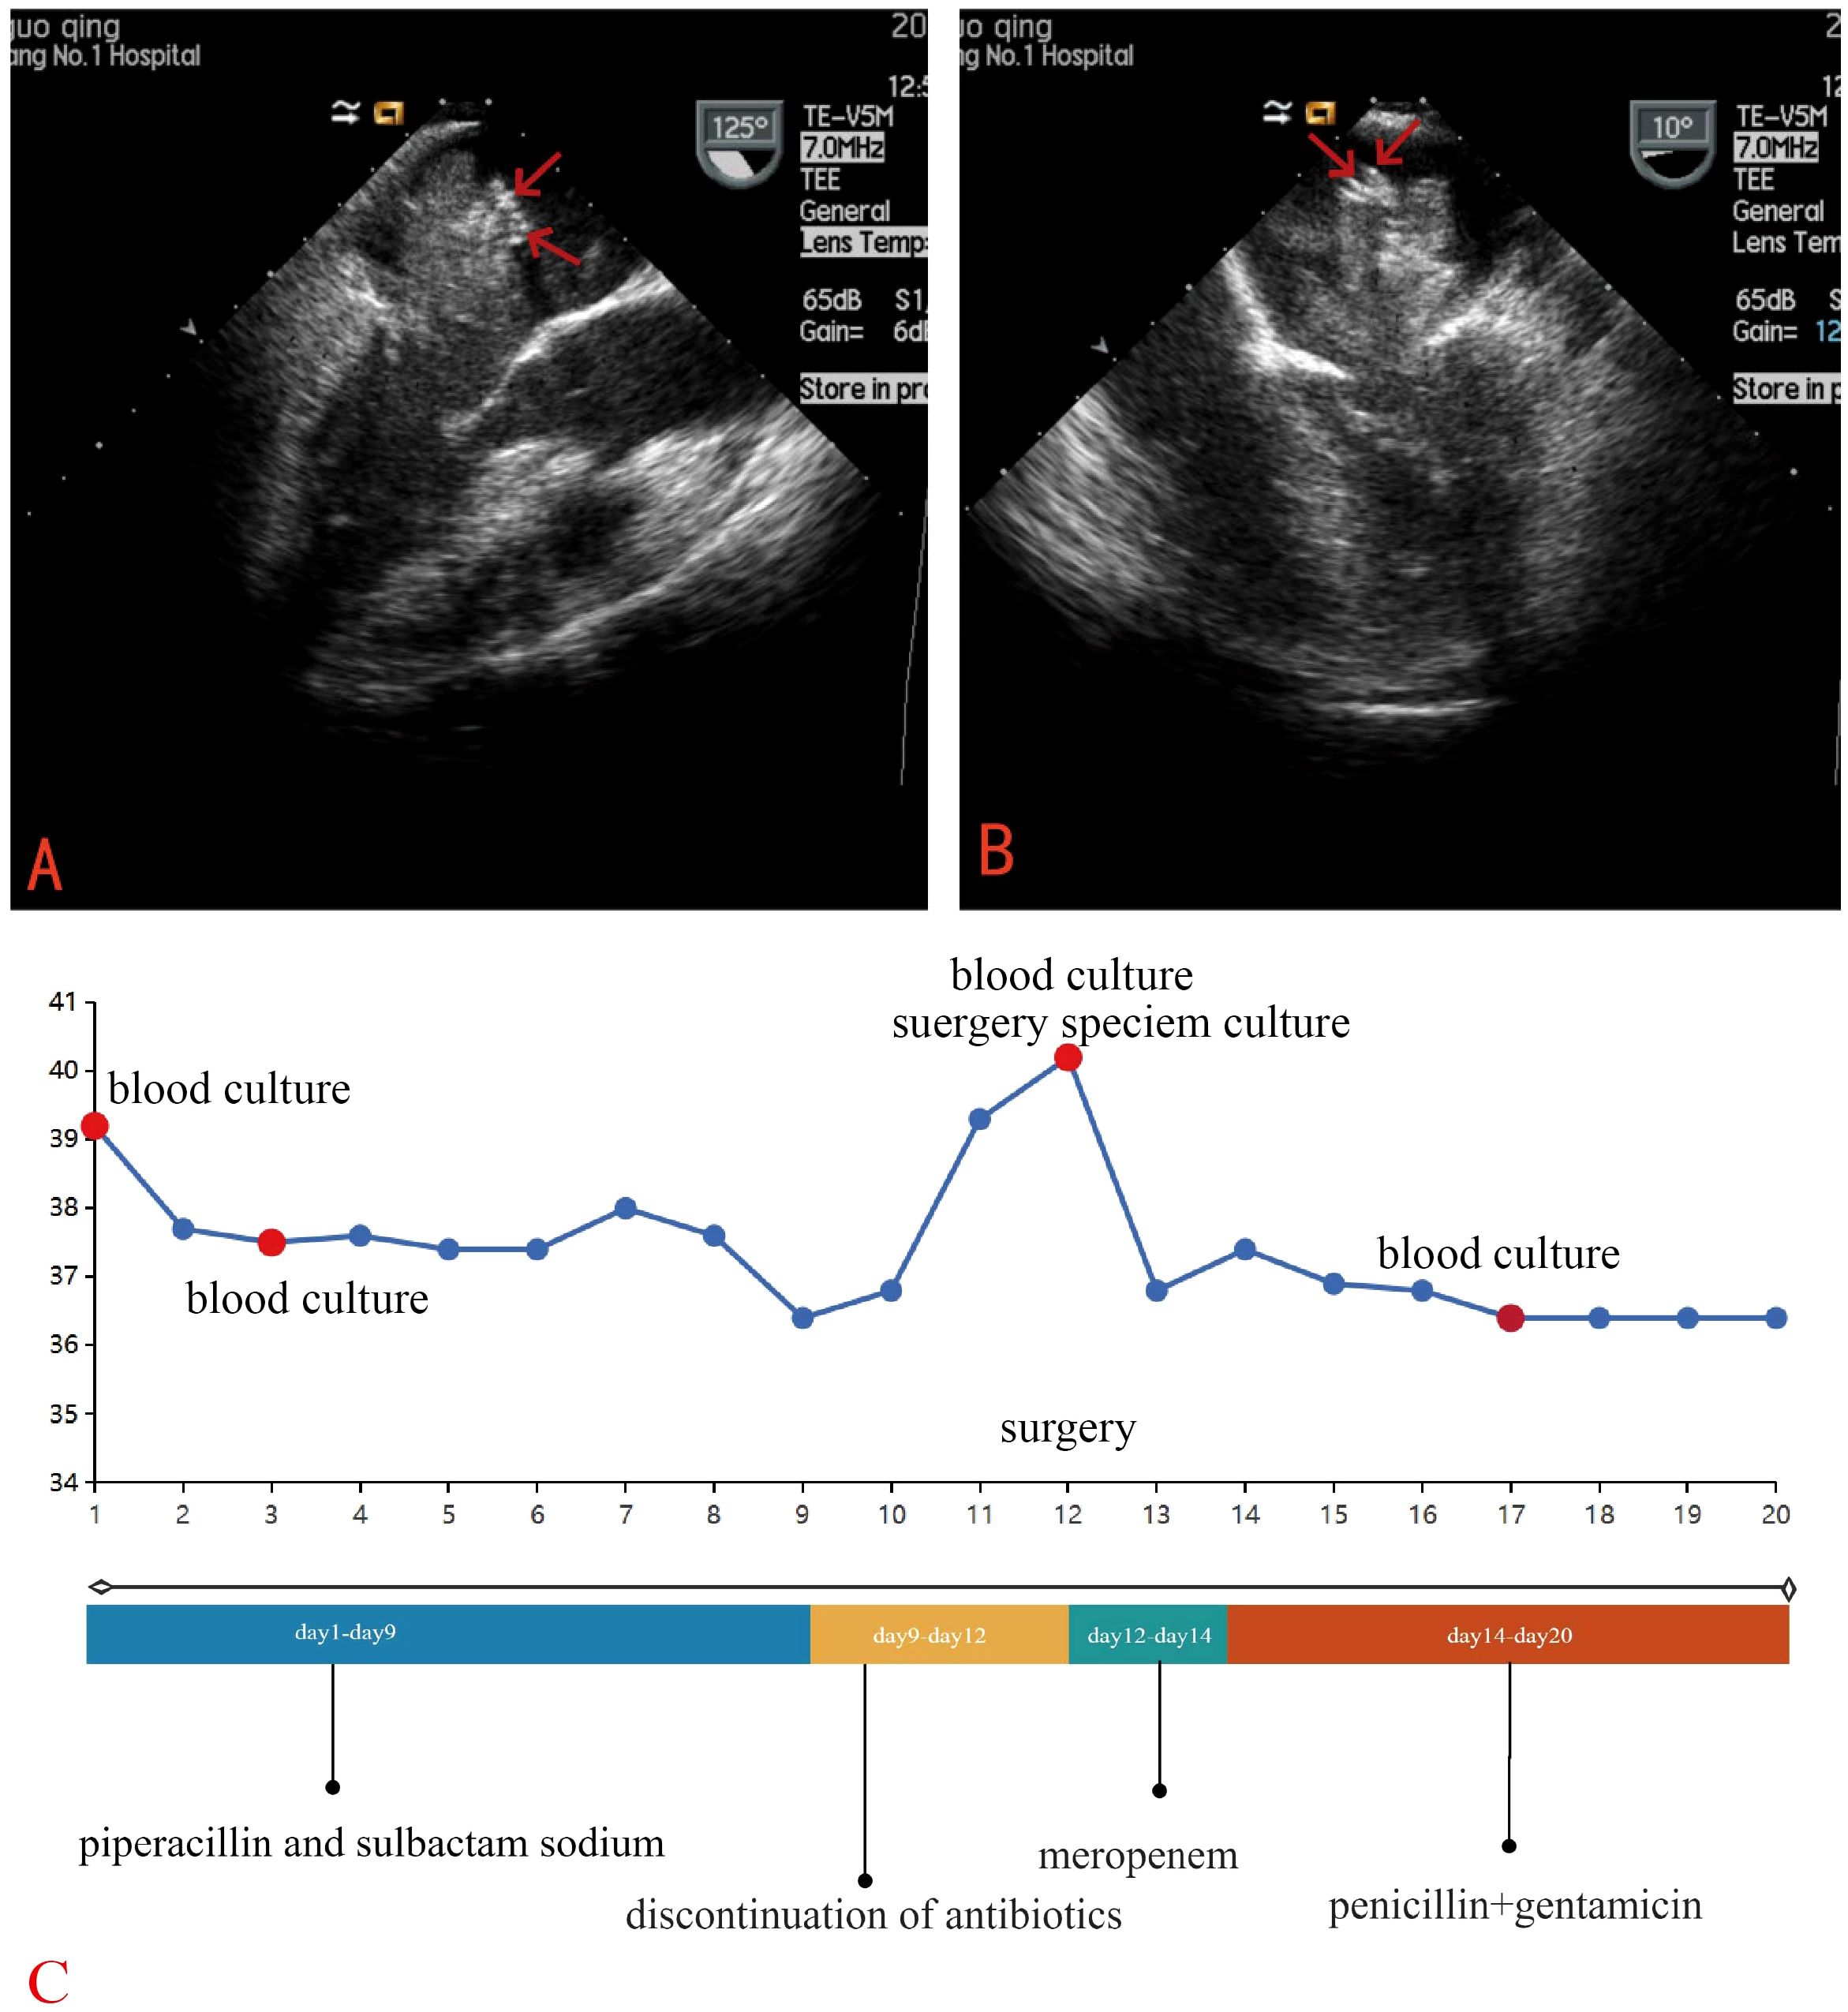

Laboratory tests revealed a raised white blood cell count of 12.58×10^9/L, with 83% polymorphonuclear cells. The hemoglobin concentration was 10.2 g/dL, and the hematocrit was 30.8%. The fasting blood glucose level was 9.73 mmol/L. Serum albumin and C-reactive protein (CRP) levels were 31.7 g/L and 16.10 mg/dL, respectively. Urine analysis showed glucose 2+ and protein 1 +. Chest computed tomography (CT) and electrocardiograms were normal. Aortic and coronary CT angiography (CTA) indicated a space-occupying lesion in the left atrium and a filling defect at the intersection of the abdominal aorta and bilateral common iliac arteries, suggestive of thrombosis (Figure 1). Transthoracic echocardiography (TTE) and TEE revealed an elongated, irregular mass originating from the fossa ovalis in the left atrium, with a base of approximately 9 mm and dimensions of approximately 7 cm × 3 cm. The tumor prolapsed into the left ventricle during diastole, causing mitral valve obstruction. TEE revealed punctate non-shadowing echogenic foci without comet tail artifact on the surface of the tumor (Figure 2; Supplementary Video 1). These findings were consistent with atrial myxoma. Additionally, the echocardiographic findings included left atrial dilation, mild to moderate tricuspid regurgitation, tachycardia, and an estimated ejection fraction of 55% in the left ventricle.

Figure 2. TEE revealed an elongated, irregular mass originating from the fossa ovalis in the left atrium, with a base of approximately 9 mm and dimensions of approximately 7 cm × 3 cm and punctate echogenic foci observed on the surface of the tumor (red arrow). (A) Long-axis view of the left ventricle (B) Four-chamber view (C) Clinical Timeline.

Empirical antibiotic therapy with piperacillin and sulbactam sodium was initiated due to the patient’s presentation of fever, cough, frequent urination, along with elevated inflammatory markers, suggesting a likely respiratory or urinary tract infection. On the third day after admission, blood cultures showed the growth of Gram-positive bacilli, which was regarded as a contaminant. A repeat blood culture was negative for bacterial growth. The patient’s body temperature gradually returned to normal. Given the likelihood that the fever was caused by the cardiac myxoma, antibiotics were discontinued after the patient was transferred to the cardiothoracic surgery department. However, following the discontinuation of antibiotics, the patient’s body temperature rose again to 39°C. The patient underwent left atrial tumor resection under cardiopulmonary bypass on the third day after the transfer. Intraoperative exploration revealed a pedunculated mass located in the fossa ovalis in the left atrium. The tumor was a lobulated, dark-red, gelatinous mass attached to the interatrial septum, with a tail-like portion exhibiting a yellow, villous mass. Multiple small vegetations were visible on the surface of the tumor (Figure 3). The tumor and a portion of the interatrial septum were resected.

Postoperatively, the patient was managed with intravenous meropenem (1 g every 8 hours) due to the suspicion of infective endocarditis (IE). On the second postoperative day, cultures of both blood and the vegetation of the surgery specimen yielded Streptococcus gordonii, which was sensitive to penicillin, vancomycin, ampicillin, ceftriaxone, cefotaxime, cefoxitin, and erythromycin. Infectious disease experts recommended treatment with penicillin (3.2 million units every 6 hours) and gentamicin. (80 mg every 12 hours). Postoperative mNGS of the patient’s blood detected both Streptococcus gordonii and Epstein-Barr virus. A transthoracic echocardiogram (TTE) performed on the fourth postoperative day showed no residual mass.

While TEE is nearly 100% sensitive for detecting cardiac myxomas, differentiating the imaging characteristics of infected and non-infected cardiac myxomas remains challenging. In this case, a retrospective review of TEE revealed intrasolid punctate nonshadowing echogenic foci without comet tail artifact on the surface of the tumor, which were interpreted as ultrasonic manifestations of tiny, nodular vegetations that were not detected by TTE. A finger-like projecting structure seen attached to the mass is considered to be TEE manifestation of a vegetation on the tumor (20). This highlights the indispensable role of TEE in identifying infections in cardiac myxomas, particularly its enhanced capability in detecting tiny vegetations.